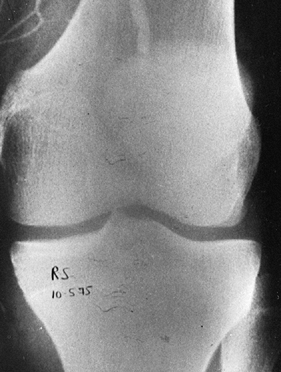

![]() |

Figure 91.4. Lateral radiograph of a posterior dislocation.